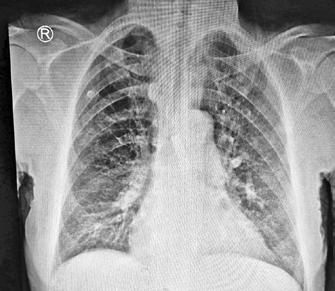

Manifestări cutanate în diabetul zaharat

Diabetul zaharat, o afecțiune metabolică complexă, cauzează hiperglicemie cronică și are un impact semnificativ asupra sănătății publice, generând costuri estimate la 412,9 miliarde de dolari în SUA în 2022. Acesta are două forme principale: tip 1 și tip 2, fiecare având implicații economice și sociale considerabile. Manifestările cutanate asociate cu diabetul, cum ar fi acanthosis nigricans, necrobioza lipoidă, bullosis diabeticorum, dermopatia diabetică, xantomatoza eruptivă și granulomul annulare, pot indica severitatea afecțiunii și complicațiile sale. Acanthosis nigricans este corelată cu hiperinsulinemia și apare adesea în zonele axilare și pliuri, în timp ce necrobioza lipoidă afectează în special membrele inferioare. Bullosis diabeticorum se manifestă prin buloase spontane fără inflamație, iar dermopatia diabetică se reflectă prin leziuni hiperpigmentate. Infecțiile cutanate, frecvente la pacienții diabetici, sunt agravate de controlul glicemic deficitar, incluzând atât infecții bacteriene cât și fungice. Reacțiile de hipersensibilitate la tratamentele antidiabetice punctează nevoia unei abordări multidisciplinare în managementul diabeticilor. Această revizuire evidențiază necesitatea examinării dermatologice în diagnosticul și monitorizarea diabetului. Cercetările ulterioare ar trebui să vizeze elucidarea mecanismelor patogenetice și dezvoltarea de strategii terapeutice personalizate pentru optimizarea controlului glicemic și pentru prevenirea complicațiilor dermatologice.

vând în vedere creșterea alarmantă a prevalenței diabetului și implicațiile socio-economice, această patologie devine o prioritate majoră pentru sănătatea publică. Este esențială implementarea unor strategii integrate care să vizeze prevenția primară, diagnosticarea timpurie și intervențiile terapeutice moderne, măsuri esențiale pentru îmbunătățirea managementului metabolic și reducerea riscului de complicații pe termen lung [3]

Examinarea dermatologică prezintă un rol important în identificarea precoce a diabetului zaharat și a prediabetului, având în vedere impactul sistemic al

acestei afecțiuni care poate determina sau debuta cu o serie de manifestări cutanate [4]. Un studiu observațional prospectiv desfășurat într-o clinică de diabetologie a demonstrat faptul că leziunile cutanate au fost prezente la peste 98% dintre pacienții cu diabet zaharat de tip 2 și la 34% dintre cei cu diabet zaharat de tip 1. Deși 98% dintre pacienții cu DZ cu o durată de peste 5 ani au prezentat manifestări cutanate, afectarea cutanată a fost totuși regăsită și la aproximativ 80% dintre pacienții diagnosticați cu DZ de mai puțin de 5 ani [5]

Modificările metabolice apărute pe parcursul evoluției diabetului favorizează dezvoltarea unor dermatoze caracteristice, cum ar fi acanthosis nigricans, necrobiosis lipoidica diabeticorum, bullosis diabeticorum, xantomatoza eruptivă și dermopatia diabetică [4] .